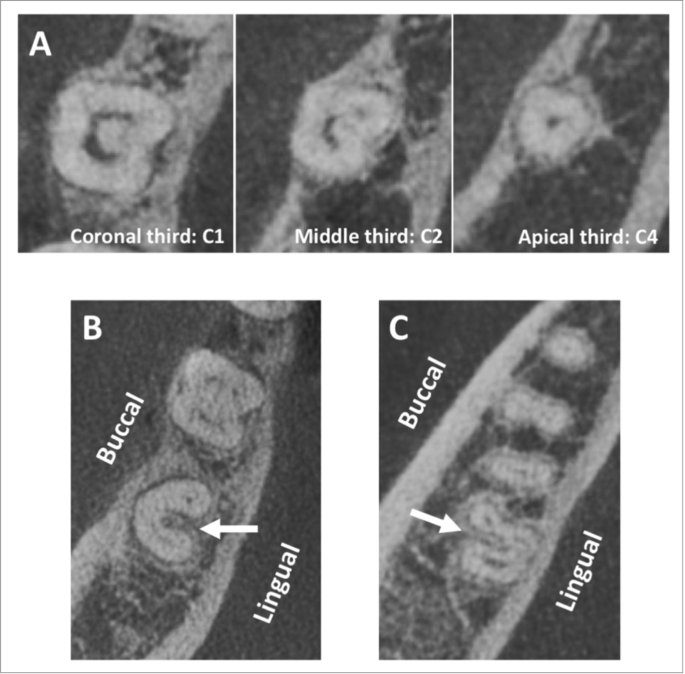

A C-shaped canal system can be observed in many variations

in root and canal morphology. It can vary along the root depth so the appearances of

the orifices are not necessarily good predictors of the actual canal anatomy.

🔴Fan et al in 2004 modified Melton’s method of classification into the following categories 🔴

1️⃣Category I (C1):

The shape is an uninterrupted “C” with no separation or division.

2️⃣ Category II (C2):

The canal shape resembles a semicolon resulting from a discontinuity in the “C” outline, but either angle α or β should be no less than 60°.

3️⃣Category III (C3):

Two or three separate canals and both angles, α and β, are less

than 60°.

4️⃣Category IV (C4):

Only one canal, which is round or oval in cross section

5️⃣Category V (C5):

No canal lumen can be observed (usually seen near the apex only).